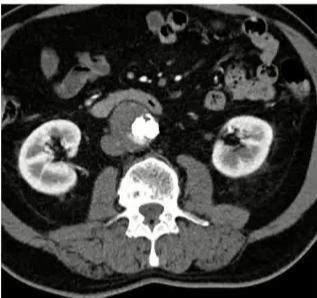

栓塞材料的可及性(例如病灶栓塞材料的可到达性)accessability (e.g. reachability of the nidus) 栓塞的预期深度intended deepness of embolization 如果需要让栓塞填满最后1mm 预期效果(例如:门静脉栓塞的炎症)intended effect (e.g. inflammation in PVE) 凝血状态(达到止血效果所需的时间)coagulation state (duration until hemostasis) 并发症(过敏、心律不齐、肺动脉高压、肝纤维化等)comorbidities (allergies, arrythmia, pulmonary hypertension, lung fibrosis etc.) 处于危险中的结构(包括下游部分-downstream和反流部分) structures at risk (downstream & backwash) 靶病变定位(浅层与深层) target lesion localization (superficial vs. deep) 不会选择一些会引起炎症的东西,因为那会病人来说真的很痛苦浅层病变 栓塞所需的速度(例如:危及生命的出血情况)required speed of embolization (e.g. life threatening hemorraghe) 院外专业人员(DSA技术人员和介入放射科医生)local expertise (technicians & IR's) 可用性与定价 availabilty & pricing Patient assessment for the choice of the ideal liquid emboli 影像学 62岁 男性